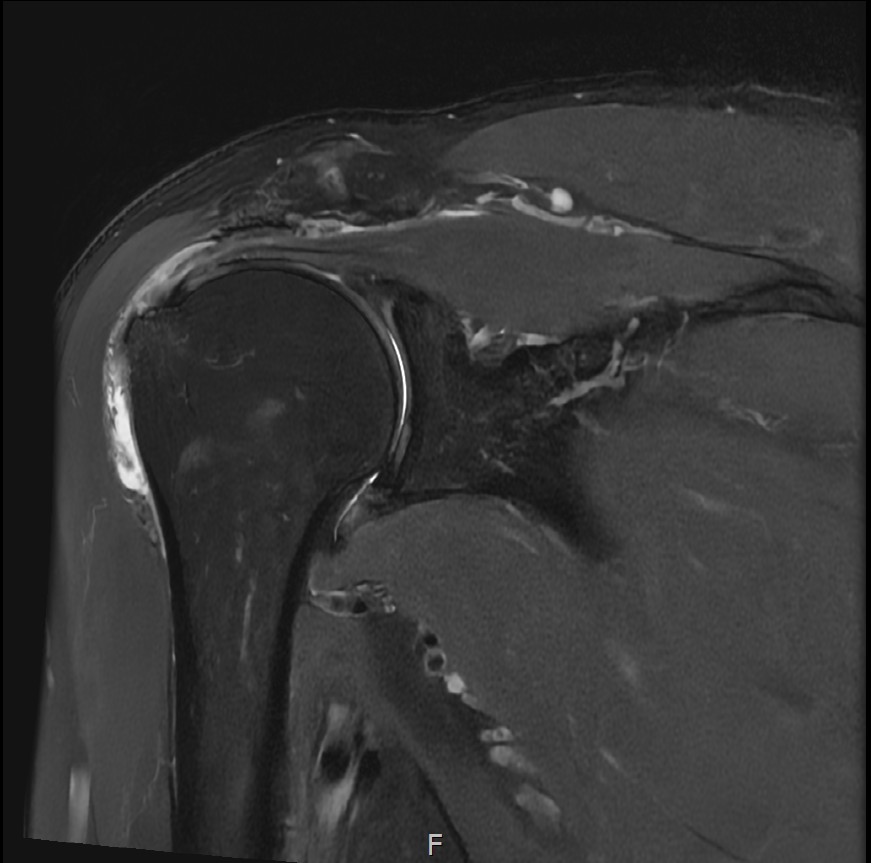

MRI를 검토해보았습니다.

회전근개 극상건의 점액낭면측(bursal-side) 부분파열. 처음보다 파열 범위가 약간 넓어져 있었고, 인대가 얇아진 소견도 보였습니다.

MRI: 극상건 점액낭면측 부분파열

인대 두께: 4.2mm (정상 5~6mm보다 얇음)

1년간 주사치료 3회, 반복 재발